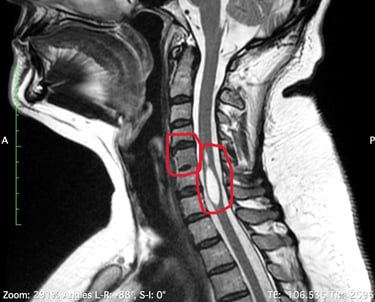

That MRI resulted on the finding of a syrinx, which is a cyst inside the spinal cord (Syringomyelia), full of cerebroespinal fluid (CSF) and obstructing the canal. The radiologist also found the fusion of two cervical vertebraes (Klippel-Feil) and led her to see a neurosurgeon who said he didn't have the experience to treat her but assured her symptoms were not related to this finding.

Her symptoms list continued to increase (weakness, numbness, dizziness, palpitations and irregular heart rate) and so the number of doctors she would see, trying to find answers, and that's when she decided to have a consultation with a doctor in the US (in July 2021) who confirmed three diagnoses: Syringomyelia, Klippel-Feil and Tethered Cord. This last anomaly was found on MRI images she had from 2019, which had been seen by several doctors (radiologists, orthopedist, neurosurgeon and family doctor) but none of them were able to see the defect.

MRI imaging is often used to evaluate people with symptoms of TSCS. Doctors can use MRI imaging to diagnose where the tethering is located, whether the base of a patient's spinal cord (the conus medullaris) is lower than normal, or if a tumor or a fatty mass (known as a lipoma) is causing the symptoms of TSCS.